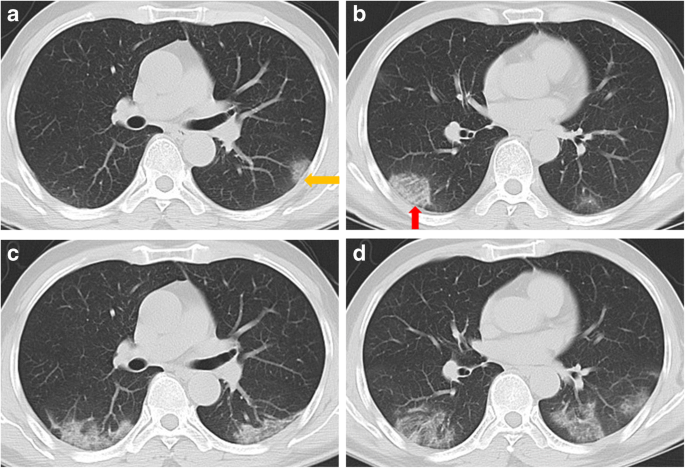

Time Course Of Lung Changes At Chest Ct During Recovery From Coronavirus Disease 2019 Covid 19 Radiology